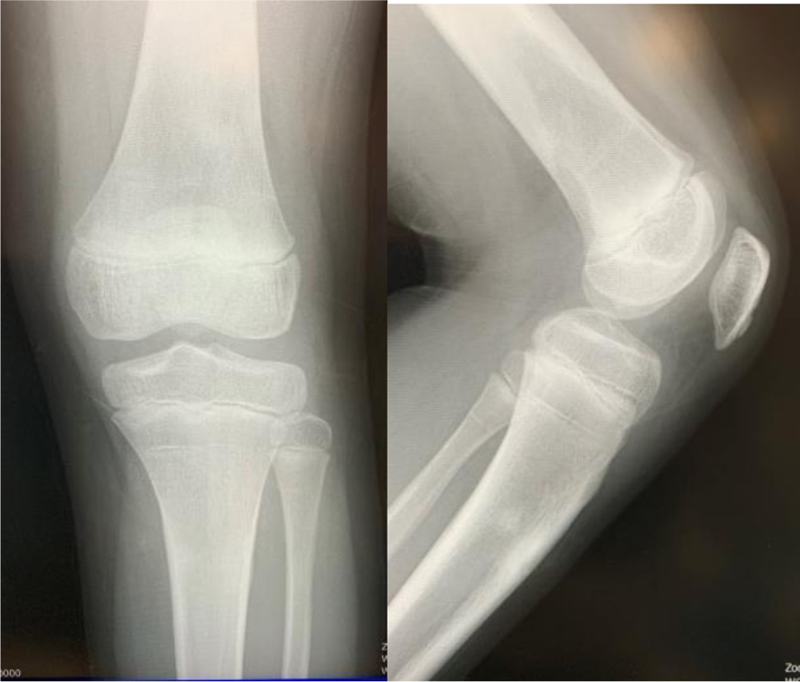

One year after surgery, he had no pain, and his knee regained full extension and 140° flexion (Fig. 3).